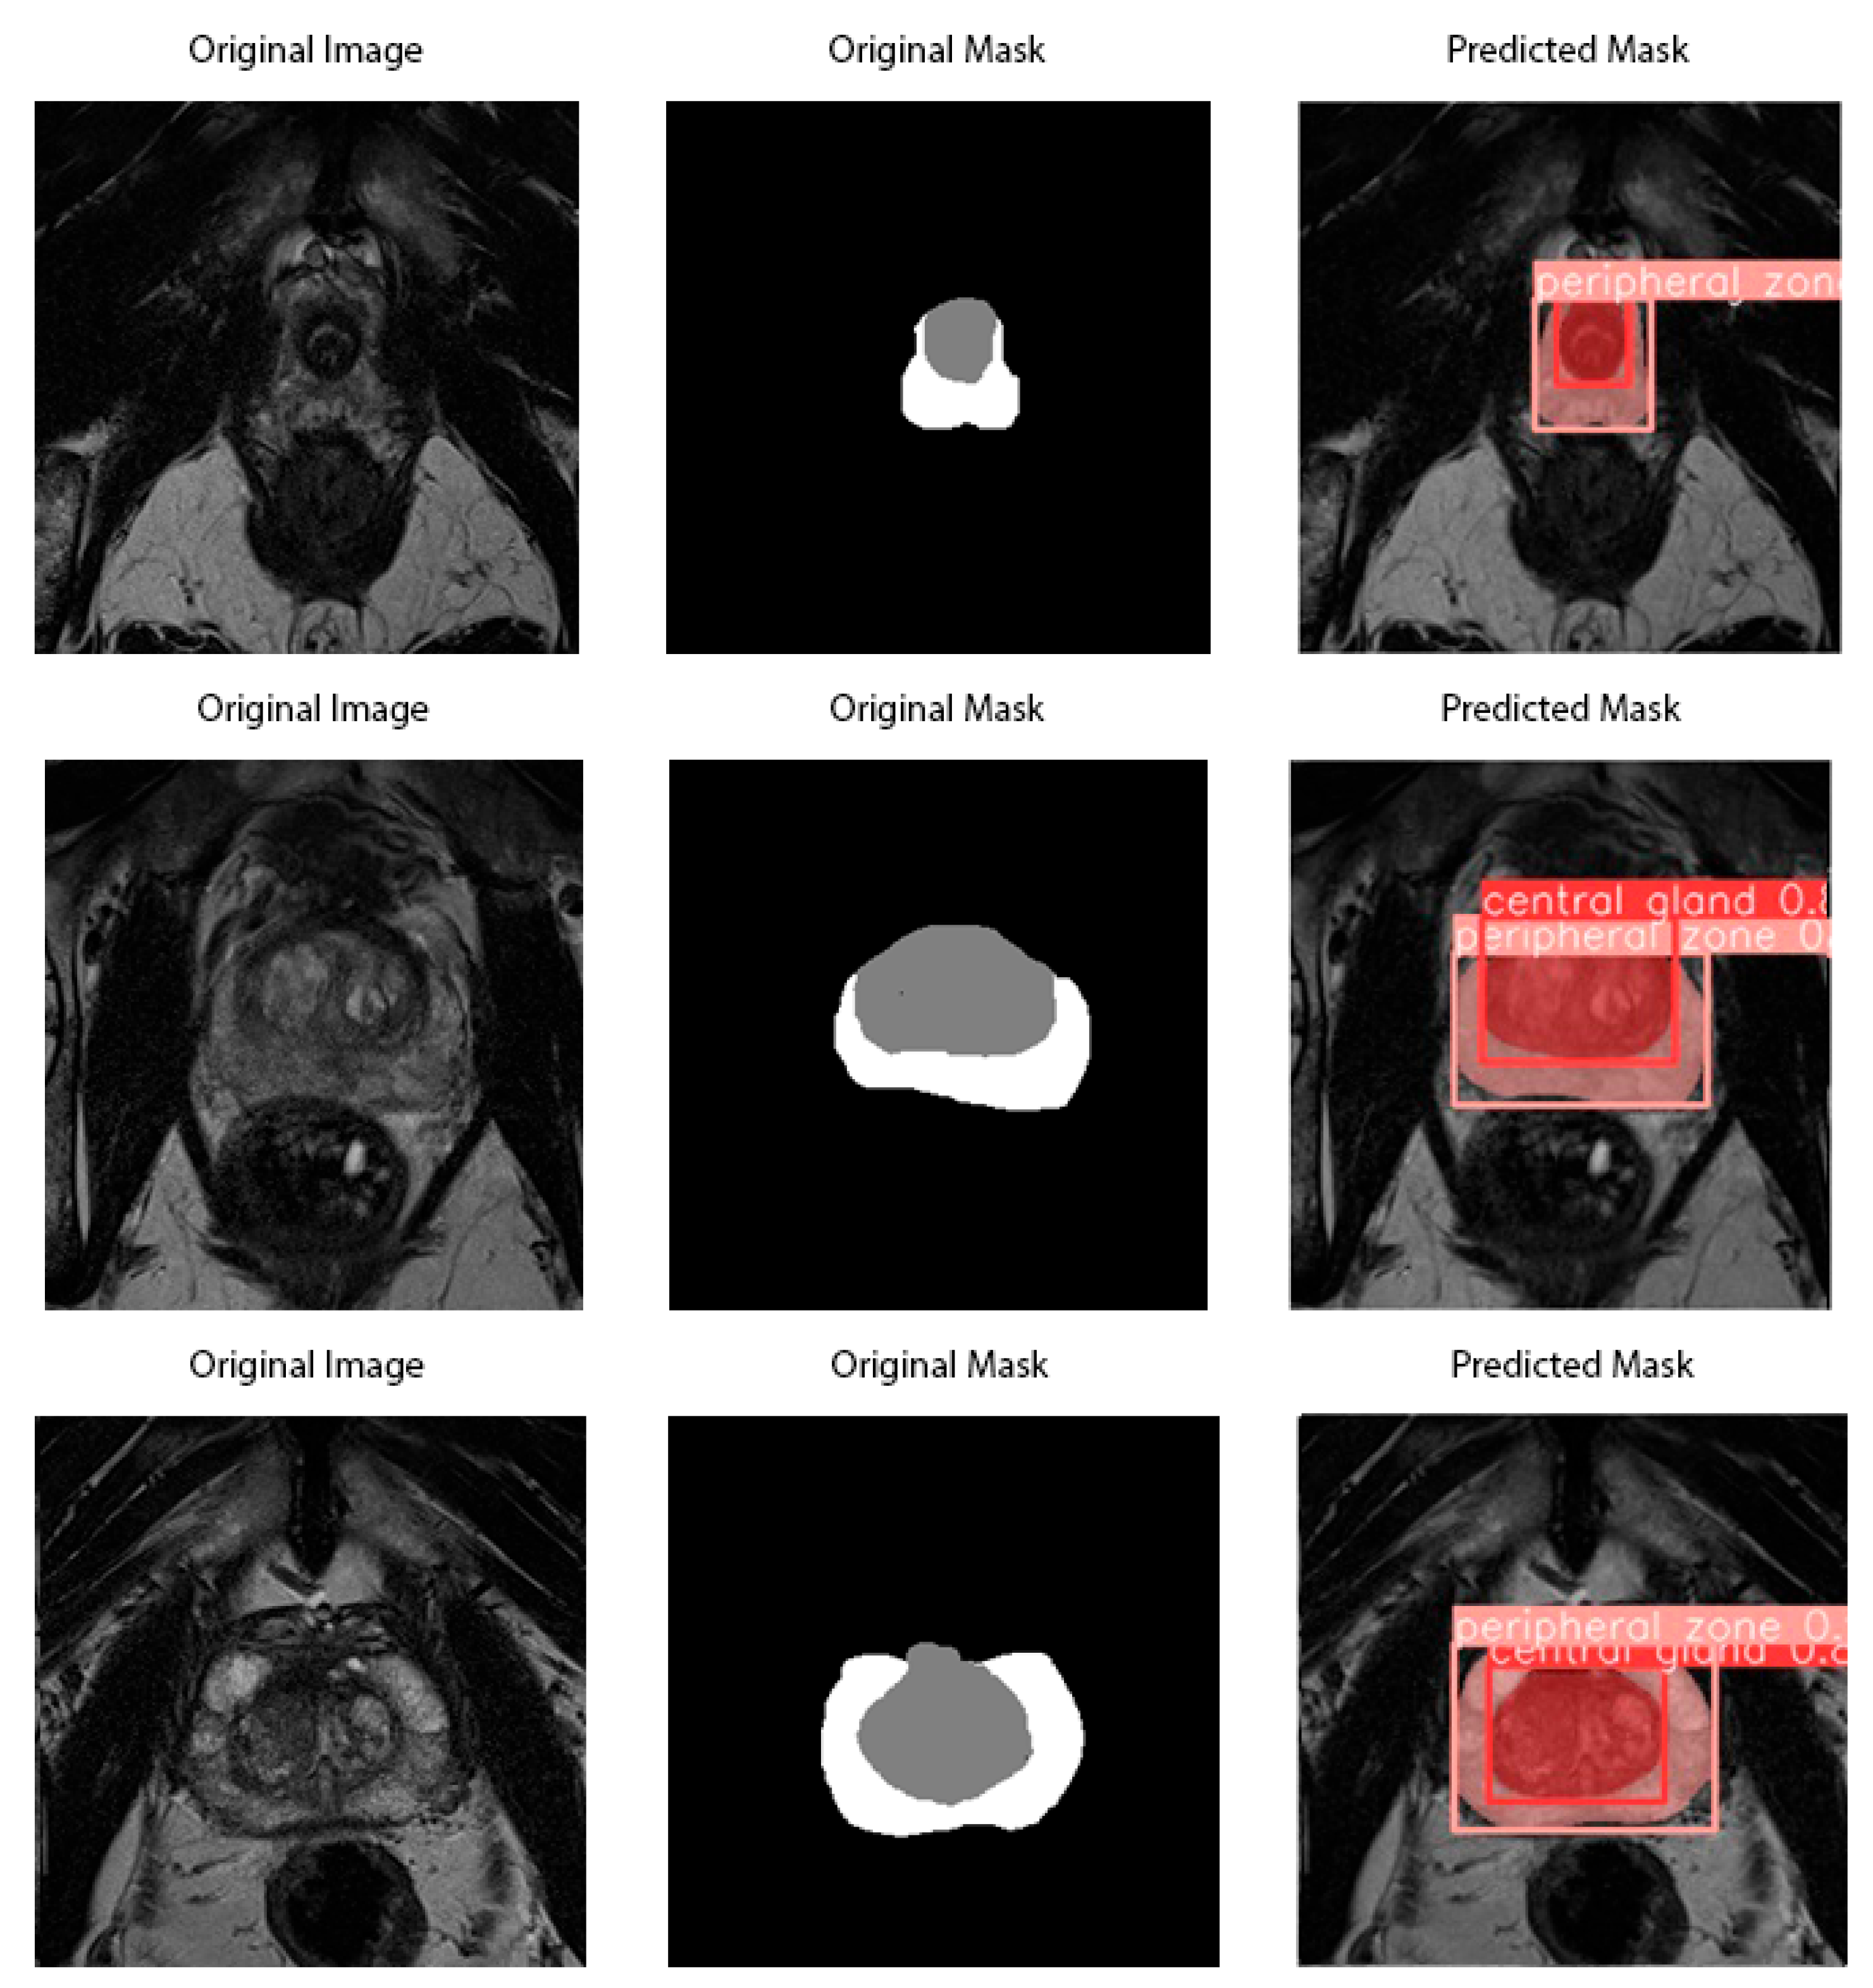

3.2.3. YOLO-V8 Architecture

4. Results